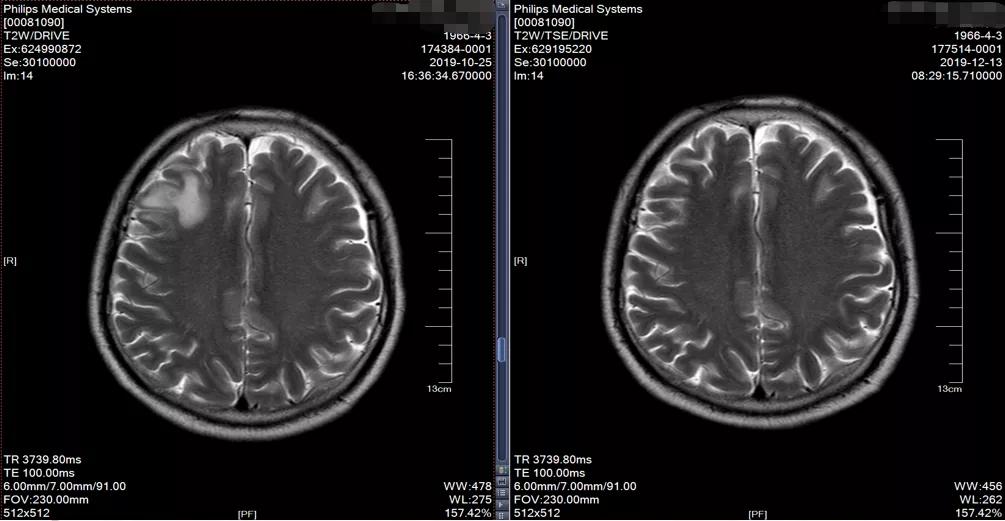

2019-10-25于广医一院行PET/CT检查考虑右上肺肺癌并右肺门、纵隔淋巴结转移。头颅MR:右侧额叶异常信号影, 考虑转移瘤。 双侧额顶叶散在缺血灶。

2019-10 头颅MRI示右额叶转移瘤,伴瘤旁水肿

2019-12-12头颅MRI示右侧额叶及左侧顶叶少许缺血灶,未见异常强化影